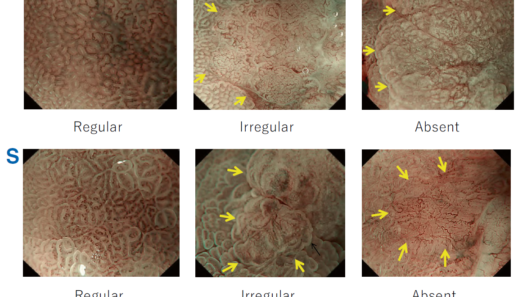

According to the morphology of the anatomical components, the MV and MS patterns were classified as regular, irregular, or absent (. Fig. 2). In principle, the MV and MS patterns must be determined separately.

DL is defined as the border between the lesion and non-lesion areas, discernible through an abrupt change in MV and/or MS patterns (. Fig. 2).

The criteria for high-grade dysplasia (HGD)/early cancer (EC) are as follows:

- Presence of an irregular MV pattern with a demarcation line.

- Presence of an irregular MS pattern with a demarcation line.

A target lesion is diagnosed as HGD/EC if it fulfills both or either of the criteria. If it does not meet either of the criteria, it is diagnosed as noncancerous.

The working group members carried out a systematic review of the English literature to determine widely accepted diagnostic systems. Consequently, the best-accepted diagnostic system was proven to be the VS classification system. Based on this system, MESDA-G was constructed using an evidence-based approach (. Figs. 3, 4, 5, and 6) [2]. First, lesions suspicious for EGC should be detected by careful inspection using conventional white-light endoscopy. Subsequently, magnified observations should be performed. Owing to the high sensitivity of the demarcation line [8], if it is absent, the suspicious lesion is diagnosed as noncancerous (. Fig. 4a, b). However, if the demarcation line is present, further assessment is required to determine the presence of an irregular MV or MS pattern. If an irregular MV and/or MS pattern is detected, the suspicious lesion is diagnosed as cancerous (. Fig. 6a, b) [1, 5, 6, 8]. If both the irregular MV and MS patterns are absent, the tumor is diagnosed as noncancerous (. Fig. 5a, b) [1, 5, 6, 8].